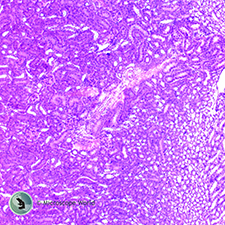

Small Mammal Kidney

This small mammal kidney prepared slide was captured under the microscope at 100x magnification.